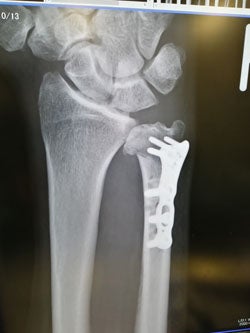

TFCC損傷尺骨突き上げ症候群druj不安定症入院手術尺骨短縮術ギプス手術跡レントゲン入院記録抜釘手術。

tfcc損傷と尺骨短縮術後㊻抜釘後その3ホンダのTFCC損傷と更年期主婦のブログ。

TFCC損傷・尺骨短縮術 入院~手術~術漁師の徒然なるブログ。

術後8ヶ月 TFCC損傷漁師の徒然なるブログ。